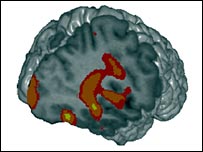

Ressonância do cérebro de um pedófilo

Áreas vermelhas indicam regiões com menos 'substância branca'

Em artigo no Journal of Psychiatry Research, os pesquisadores explicam que os pedófilos estudados apresentavam menos quantidade da chamada "substância branca", responsável por fazer as ligações internas entre diferentes partes do cérebro envolvidas na excitação sexual.

Os estudiosos descobriram que algumas regiões dos cérebros dos pedófilos mostravam menos sinais de atividade do que os de outros voluntários, quando eram estimulados com material erótico.